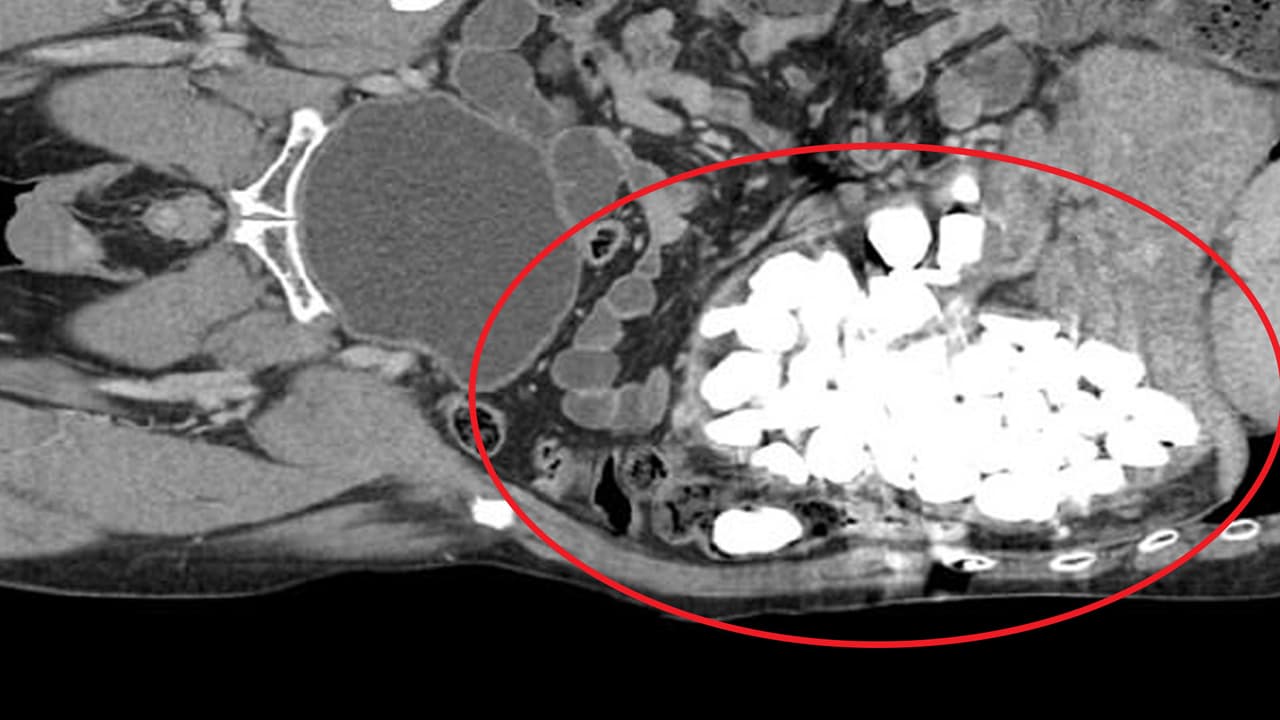

Encuentran piedras, corchos y monedas en el estómago de un hombre

El paciente fue intervenido debido a fuertes dolores abdominales por objetos extraños en el estómago, todo ello al parecer debido a la ansiedad.